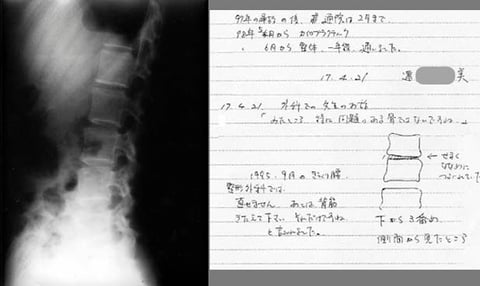

その数年後、その方からレントゲンが送られてきました。

右がコメントですが、事故当時アメリカの病院で下から3番目を潰していたのを確かに見たということでした。「どおりで痛くないはずだ」というコメントでした。背骨の並びもさることながら何が起こったのか不明です。